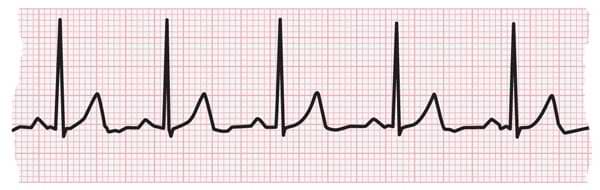

ECG strip showing bradycardia

Bradycardia is a heart rate that’s too slow. A normal average heart rate is 60-100 beats per minute. What’s considered too slow can depend on your age and physical condition. Elderly people, for example, are more prone to bradycardia.

An adult resting heart rate of fewer than 60 beats per minute (BPM) qualifies as bradycardia.